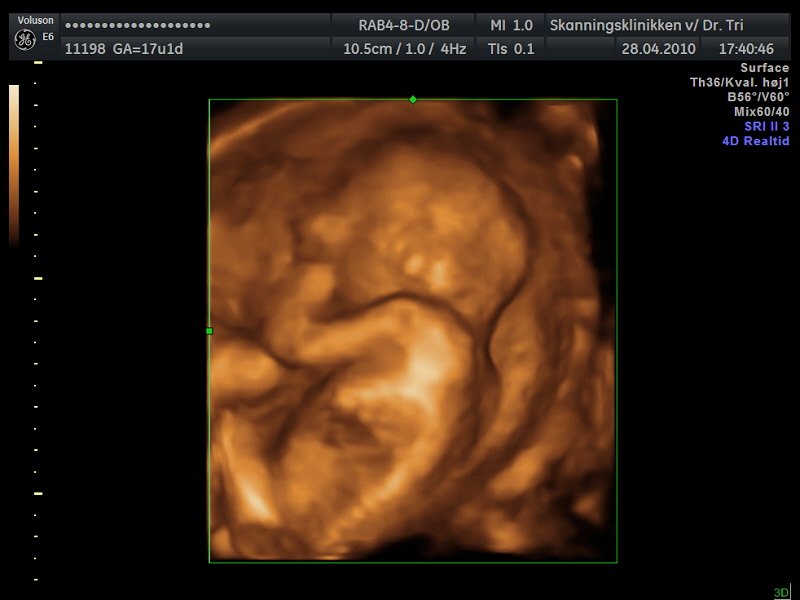

Desværre lå moderkagen foran så billederne blev ikke ret gode men her er et par stykker:

Min moderkage ligger nemlig også foran, men syntes stadig at billederne er helt fine